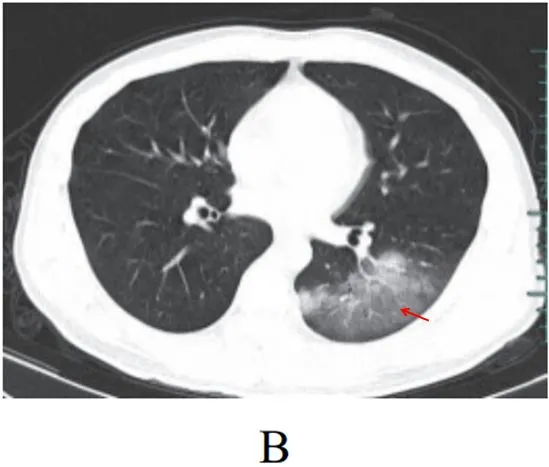

病灶形态以三种类型为主,即多叶多灶分布病灶(图 2-2A) 、单叶片状病灶(图 2-2B)和孤立性类圆形病灶(图 2-2C)

多叶多灶分布病灶(图 2-2A)

单叶片状病灶(图 2-2B)

孤立性类圆形病灶(图 2-2C)